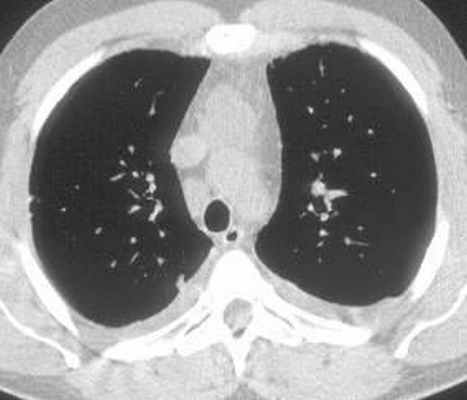

Больной С., 33 г., по профессии электромонтажник, поступил в НМХЦ им. Н.И. Пирогова 5 февраля 2007 г. с жалобами на одышку при незначительной физической нагрузке, кашель с трудноотделяемой мокротой слизистого характера, общую слабость, похудание на 10 кг, субфебрильную температуру тела. С 2000 г. у пациента диагностировали хронический ринит, синусит, полипоз носа. Для купирования затрудненного носового дыхания последние 3 года применял кортикостероидный назальный спрей. В связи с возникновением приступов удушья 2006 г. в НИИ аллергологии и иммунологии диагностирована бронхиальная астма среднетяжелого течения. Назначена терапия симбикортом с положительным эффектом. Ухудшение состояния с декабря 2006, когда появились субфебрильная температура тела, приступы затрудненного дыхания, одышка при физической нагрузке, снижение аппетита. При КТ органов грудной клетки, выполненной амбулаторно 25.01.07г.: лимфаденопатия средостения (лимфоузлы до 2-2,5 см) с образованием конгломерата размером 38 х 40 х 50 мм (рис. 1), снижение прозрачности легочной ткани по типу «матового стекла» (рис. 2а), диффузное уплотнение интерстициальной ткани (рис. 2б), двусторонний гидроторакс. Заподозрена опухоль переднего средостения в связи, с чем пациент госпитализирован для морфологической верификации диагноза.

| Рис. 2. КТ грудной клетки: а - снижение прозрачности по типу “матового стекла“, б - диффузное уплотнение интерстициальной ткани. | |